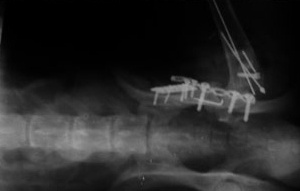

Слева - Портография спаниеля. Портоковальный шунт.

В центре - Повторная портография спаниеля.

Справа - Портография овчарки в начальной стадии цирроза печени. Расширение сосудов.

Слева - Портография спаниеля. Портоковальный шунт. В центре - Повторная портография спаниеля. Справа - Портография овчарки в начальной стадии цирроза печени. Расширение сосудов.